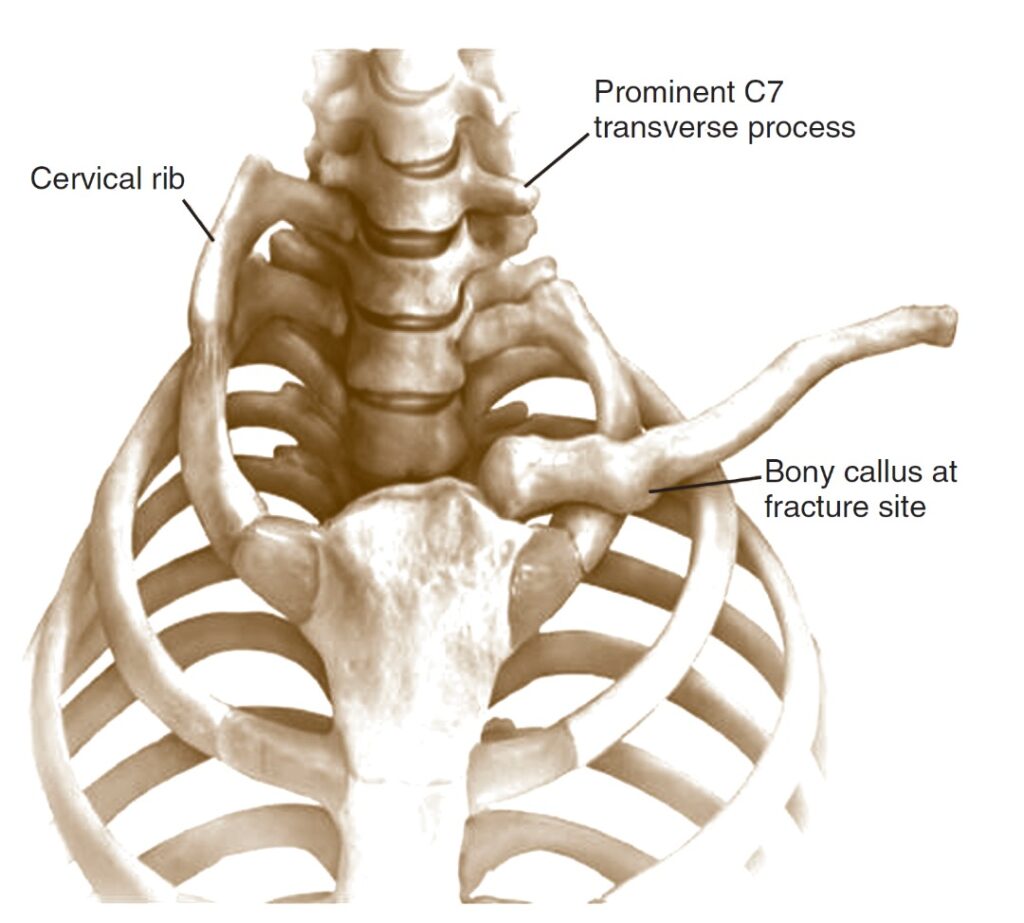

قیمت: 52٬500 تومان - دسته بندی فایل: علوم پزشکیدانلود پاورپوینت سندروم خروجی توراکس چیست

خرید پاورپوینت حرفه ای با موضوع سندروم خروجی توراکس چیست با قیمت استثنایی از لوکس فایل